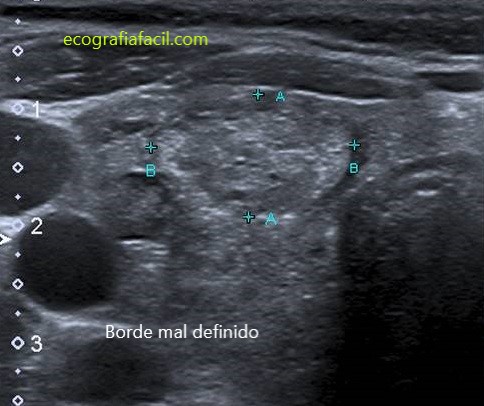

MAL DEFINIDO:

4. POR SU MARGEN:

LISO:

LOBULADO:

IRREGULAR: